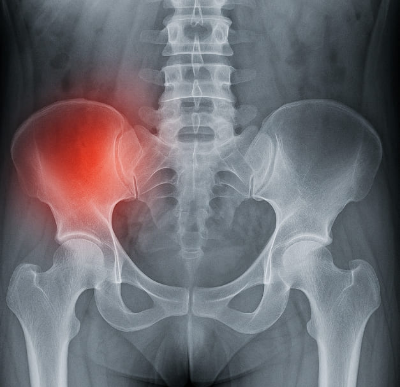

골반 통증 원인 골반 통증이란 무엇인가?

골반 통증은 하복부, 즉 배꼽 아래에서 고관절 위까지의 부위에서 발생하는 불쾌감이나 통증을 말합니다. 이 부위에는 생식기, 방광, 장, 골반 뼈와 근육, 신경 등이 밀집해 있어 다양한 원인으로 골반 통증이 발생할 수 있습니다. 골반 통증 원인을 명확히 아는 것은 정확한 진단과 치료로 이어지기 때문에 매우 중요합니다.

- 근골격계 원인: 엉덩이 근육통, 이상근 증후군, 고관절 질환, 천장관절 이상 등